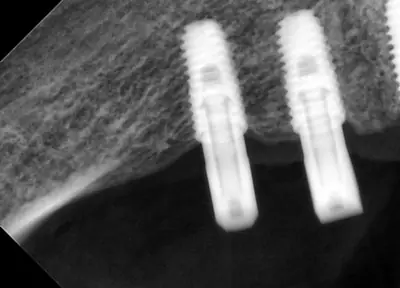

치과 치료를 두려워하는 분들에게 희망적인 사례를 소개합니다. 부산에 거주하던 60대 여성 환자가 치과 공포로 치료를 미루다 치아 상태가 악화되어, 의식하 진정요법을 통해 안전하게 임플란트 치료를 받은 이야기입니다. 환자는 병원 트라우마와 주사 공포, 치과 공포증이 있었지만, 전문의의 세심한 관리와 진정요법 덕분에 큰 불안 없이 치료를 마칠 수 있었어요. 치료 과정은 발치, 임플란트 수술, 인상 채득, 보철물 장착까지 단계별로 진행되었으며, 치료 후 자연스럽고 안정된 치아와 잇몸 라인을 확인할 수 있었습니다. 이 사례는 치과 공포증이 심한 분들도 적절한 진정요법과 신뢰를 바탕으로 치료받을 수 있음을 보여줍니다. 먼 거리에서도 찾아오는 환자들이 많은 이유는 바로 이런 진심 어린 진료와 결과 덕분이죠. 치과 치료에 대한 두려움이 있다면, 전문가와 상담하여 적합한 방법을 찾는 것이 중요합니다.